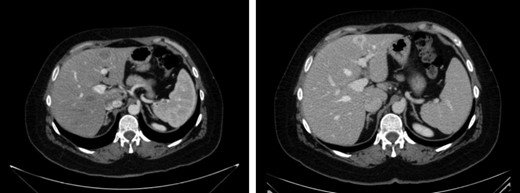

A new hepatic node in segment VII was observed nine months later (Fig. 3). Systemic treatment was administrated with cisplatin (75 mg/m2) and cetuximab for three months. At the end of the treatment, another non-anatomical metastasectomy with free margins was performed.